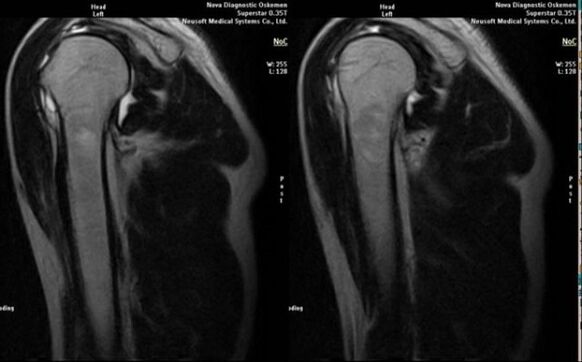

- magnetic resonance and computed tomography;

Signs that directly indicate the development of arthropathy include significant narrowing of the joint space, sclerosis of the subchondral structures, thinning of the chondrocyte layer itself, the appearance of osteophytes, and the deposition of salt crystals in the intraarticular fluid.